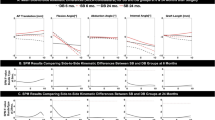

The mean magnitude of tibial AP translation (range minimum to maximum AP position) analyzed by the 2D/3D registration technique was 5.23 ± 2.70 mm in ACLD knees, 5.15 ± 3.84 mm in the contralateral knees, and 4.27 ± 2.34 mm in DB-ACLR knees; there were no significant differences. The AP position of the tibia of the ACLD knees was significantly different from that of the contralateral knees (p = 0.015) and the DB-ACLR knees (p < 0.001) on post hoc pairwise comparisons with a mixed linear model with repeated measures on SPSS. There was no significant difference in the AP position of the tibia between DB-ACLR knees and contralateral knees. The AP position of the tibia of ACLD knees was more anterior than that of contralateral knees at all flexion angles. The AP positions of the tibia of DB-ACLR knees were posterior to those of ACLD knees at all flexion angles. In addition, the AP positions of the tibia of DB-ACLR knees were more posterior to those of contralateral knees at 0°–60° of knee flexion, and they were almost the same at angles larger than 65° (Fig. 4).

Anteroposterior translation of the tibia analyzed by 2D/3D registration technique. Y-axis: tibial anterior translation (mm). X-axis: knee flexion angle (°). Dotted line: ACLD knees. Dashed line: DB-ACLR knees. Solid line: contralateral knees. The anteroposterior position of the tibia of the ACLD knees is significantly different from the contralateral knees and the DB-ACLR knees (post hoc pairwise comparisons with a mixed linear model with repeated measures on SPSS, p = 0.015)

The mean magnitude of the tibial rotation angle (range minimum to maximum rotational position) was 14.91° ± 6.64° in ACLD knees, 14.54° ± 5.51° in contralateral knees, and 12.87° ± 6.92° in DB-ACLR knees; there were no significant differences. The rotational position of the tibia of the ACLD knees was significantly different from that of the contralateral knees (p < 0.001) and the DB-ACLR knees (p < 0.001) on post hoc pairwise comparisons using a mixed linear model with repeated measures on SPSS. There was no significant difference in the rotational position of the tibia between DB-ACLR knees and contralateral knees. The tibial positions were more internally rotated in ACLD knees than in contralateral knees at all flexion angles. The tibial rotational positions of DB-ACLR knees and contralateral knees were almost the same at all flexion angles (Fig. 5).

Rotation of the tibia analyzed by 2D/3D registration technique. Y-axis: tibial internal rotation (°). X-axis: knee flexion angle (°). Dotted line: ACLD knees. Dashed line: DB-ACLR knees. Solid line: contralateral knees. The rotational position of the tibia is significantly different between ACLD knees and contralateral knees, and between ACLD knees and DB-ACLR knees (post hoc pairwise comparisons with a mixed linear model with repeated measures on SPSS, p < 0.001)